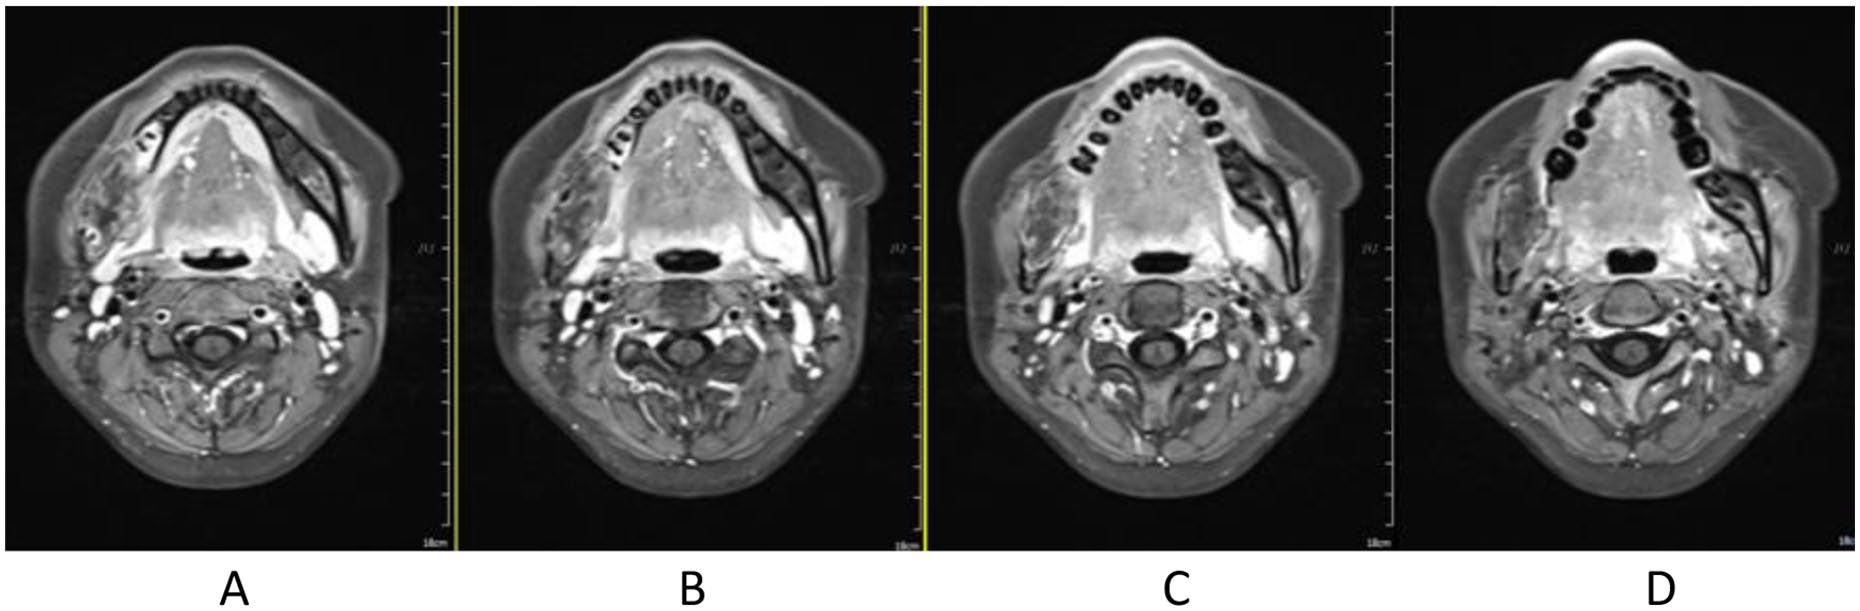

Treatment was tolerated well. During and after CIRT, there was only grade 2 skin (Figure 2) and oral mucosa acute adverse event, and no grade ⩾3 RTOG acute effect. During and after CIRT, her pain in the right mandible is continued but never aggravated, but painkiller is not needed; 6-month post completion of radiotherapy, she was in a very good clinical state, and the pain in the right mandible resolved completely. One to three months after CIRT, there were no significant changes of tumor size on MRI (Figures 3–6), just intensity of contract enhancement gradually diminished on contract-enhanced T1-weighted MRI; from 6months on, the size of the tumor decreased gradually (Figure 7); up to 16months after CIRT, it regressed to 3.6cm×3.2cm×1.7cm; and on 19months after CIRT, it regressed to 3.6cm×3.2cm×1.7cm, and the efficacy evaluation is PR (partial response) (Figures 8–10).

Figure 9. 16 months after CIRT.

Figure 10. 19 months after CIRT.